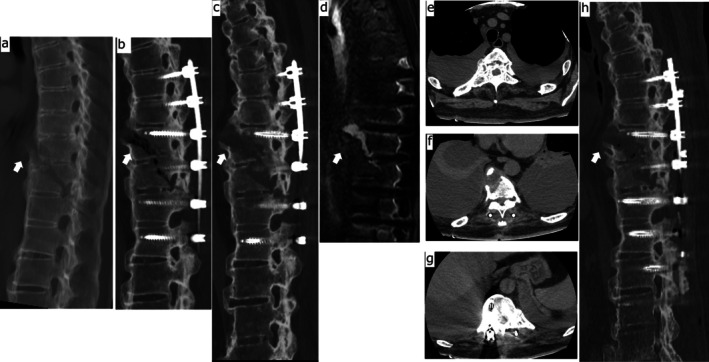

一例71岁男性弥漫性特发性骨骼肥厚症(DISH)患者因跌倒导致胸椎融合段骨折,接受后路脊柱固定治疗。术后1个月,患者因双侧大量胸腔积液和骨折部位移位较术后立即增加而再次入院。渗出性积液以淋巴细胞为主。进一步的评估表明,由于脊柱不稳定引起的炎症和胸膜刺激是可能的原因。翻修固定导致积液的溶解。低能量创伤引起的椎体骨折,如跌倒,很少导致脊柱不稳定,严重到足以引起胸腔积液,即使在不愈合的情况下也是如此。然而,由于脊柱强直和骨骼脆弱,DISH患者更容易发生高度不稳定骨折。即使在手术固定后,这种骨折也可能进一步发展为不稳定。我们报告一个病例,这种不稳定性导致局部炎症和胸膜刺激,最终导致双侧胸膜积液。DISH常见于老年人,与肥胖和糖尿病有关。据报道,其流行率正在上升。因此,内科医生和骨科医生都应该意识到类似病例的可能性,并在鉴别诊断和处理不明原因的胸腔积液时考虑与DISH相关的脊柱不稳定。

A 71-year-old man with diffuse idiopathic skeletal hyperostosis (DISH) underwent posterior spinal fixation for a thoracic vertebral fracture at a fused segment, sustained as a result of a fall. One month postoperatively, he was readmitted due to bilateral massive pleural effusions and increased displacement at the fracture site compared to the immediate postoperative state. The effusions were exudative and lymphocyte-predominant. Further evaluation suggested that inflammation and pleural irritation due to spinal instability were the likely causes. Revision fixation led to the resolution of the effusions. Vertebral fractures caused by low-energy trauma, such as a fall, rarely result in spinal instability severe enough to cause pleural effusion, even in cases of nonunion. However, patients with DISH are more prone to highly unstable fractures due to spinal ankylosis and bone fragility. Even after surgical fixation, such fractures may progress to further instability. We report a case in which this instability led to localised inflammation and pleural irritation, ultimately resulting in bilateral pleural effusions. DISH is commonly seen in older adults and has been associated with obesity and diabetes mellitus. Its prevalence is reportedly increasing. Therefore, both internists and orthopaedic surgeons should be aware of the potential for similar cases and consider spinal instability related to DISH in the differential diagnosis and management of unexplained pleural effusions.